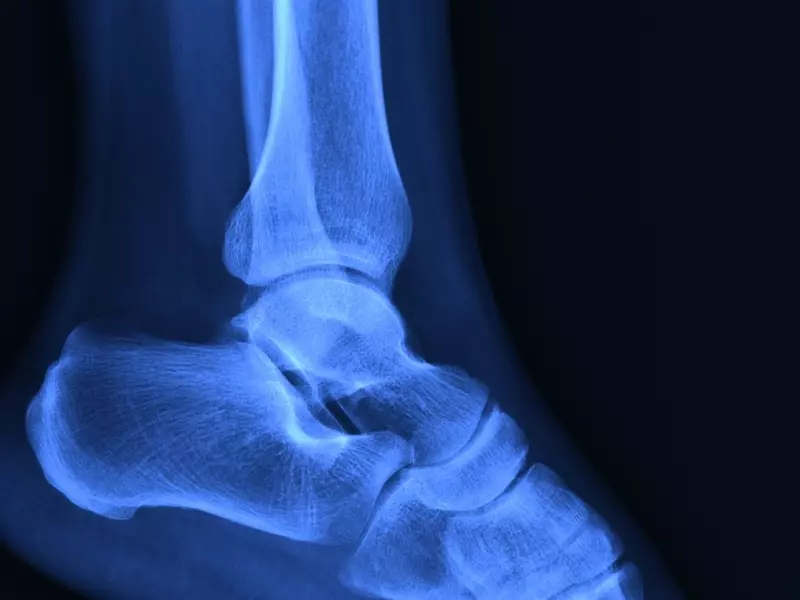

Staw skokowy jako całość należy do stawów bardzo złożonych, wielopłaszczyznowych, o dużym zakresie ruchomości. W jego skład wchodzi aż pięć komponentów kostnych – kości: piszczelowa, strzałkowa, skokowa, piętowa oraz łódkowata. Pierwsze trzy kości tworzą funkcjonalnie tzw. staw skokowy górny (skokowo-goleniowy), w którym końce dalsze kości goleni, tworząc kostkę przyśrodkową i boczną, niczym widełki obejmują bloczek kości skokowej. Dzięki takiej budowie zachodzi ruch zgięcia grzbietowego i podeszwowego (ruch zawiasowy). Staw skokowy dolny tworzą kości skokowa i piętowa (staw skokowy tylny) oraz kości skokowa i łódkowata (staw skokowy przedni). Oba stawy tworzą funkcjonalną i biomechaniczną całość i biorą udział w ruchu supinacji (sprzężony z przywiedzeniem stopy i zgięciem podeszwowym) oraz pronacji (sprzężony z odwiedzeniem stopy i zgięciem grzbietowym). Połączenie ruchu w obu stawach umożliwia ruch obwodzenia stopy (zdj. 1).